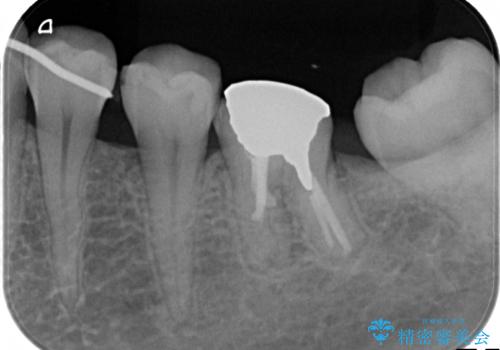

- 下顎の銀歯と、かぶせ物が外れたままになっている歯の治療を主訴に来院されました。

左下の奥歯はかぶせ物が外れて、土台が露出している状態でした。

セラミッククラウンにて下顎の左右の歯にセラミッククラウンを装着する計画としました。